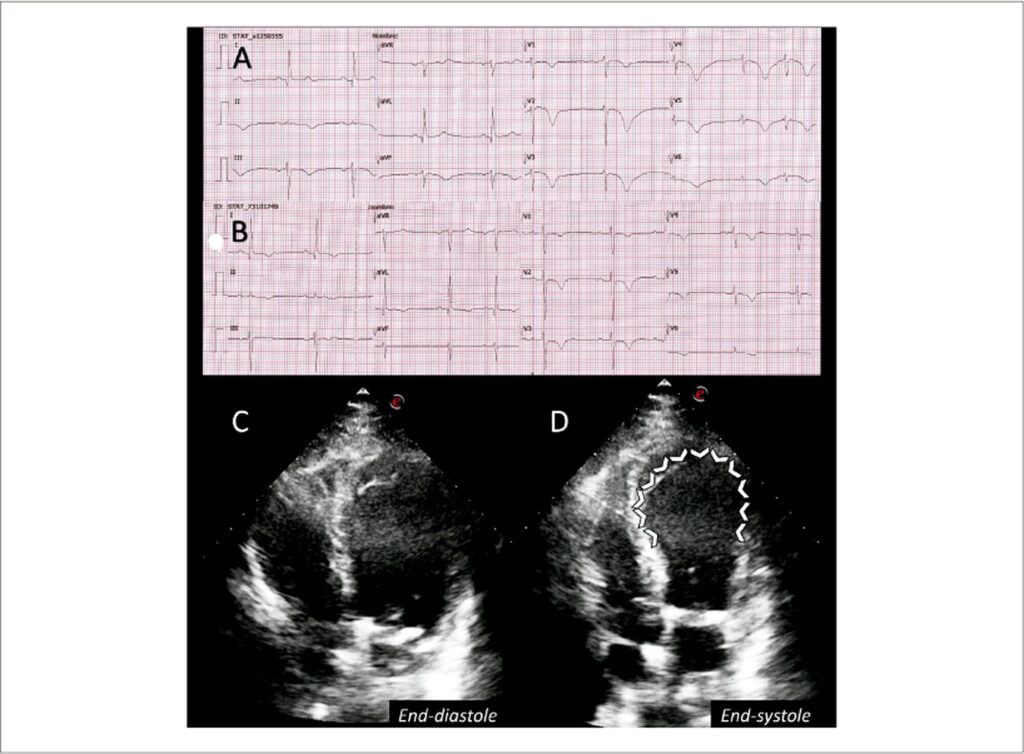

Síndrome de Takotsubo em um Paciente Crítico com COVID-19: Evolução Eletrocardiográfica e Ecocardiográfica

Por sua semelhança com uma armadilha de polvo tradicional japonesa, ou seja, um takotsubo, Hikaru Sato descreveu o primeiro caso de “cardiomiopatia de Takotsubo” em um paciente sem estenose coronariana e balonamento apical sistólico final do ventrículo esquerdo na ventriculografia cardíaca esquerda.A síndrome de Takotsubo (STT) é uma síndrome clínica caracterizada por uma disfunção sistólica ventricular esquerda aguda e transitória relacionada a um evento estressante, emocional ou físico. A COVID-19 é um gatilho reconhecido para a STT, sendo o enorme stress emocional causado pela pandemia e todo o espectro de danos miocárdicos associados ao SARS-COV-2 as possíveis explicações.